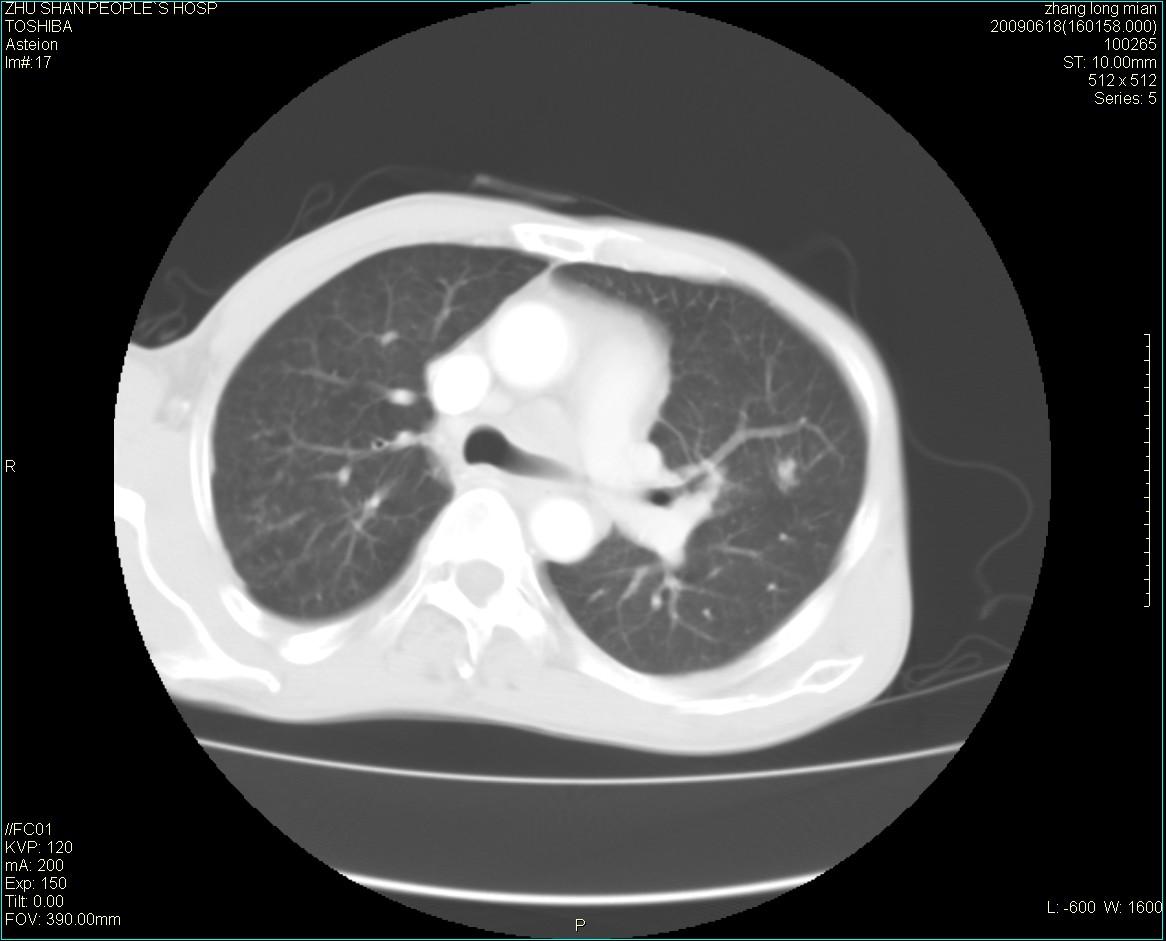

男性 65岁 胸片发现右下肺包块.诊断肺ca并纵隔转移没有问题吧!

肺ca并纵隔转移,阻塞性炎症。

两侧胸廓不对称,右侧呈塌陷改变,右肺萎缩。

右下肺见浅分叶状软组织块影,边缘有毛刺,其下部似见不完整偏心空洞影,邻近胸膜凹陷征,并胸腔积液。

增强见纵隔区气管隆突上下及左肺门区肿大淋巴结。左肺感染性病灶。

另见右上肺见一枚小结节影,性质待定。